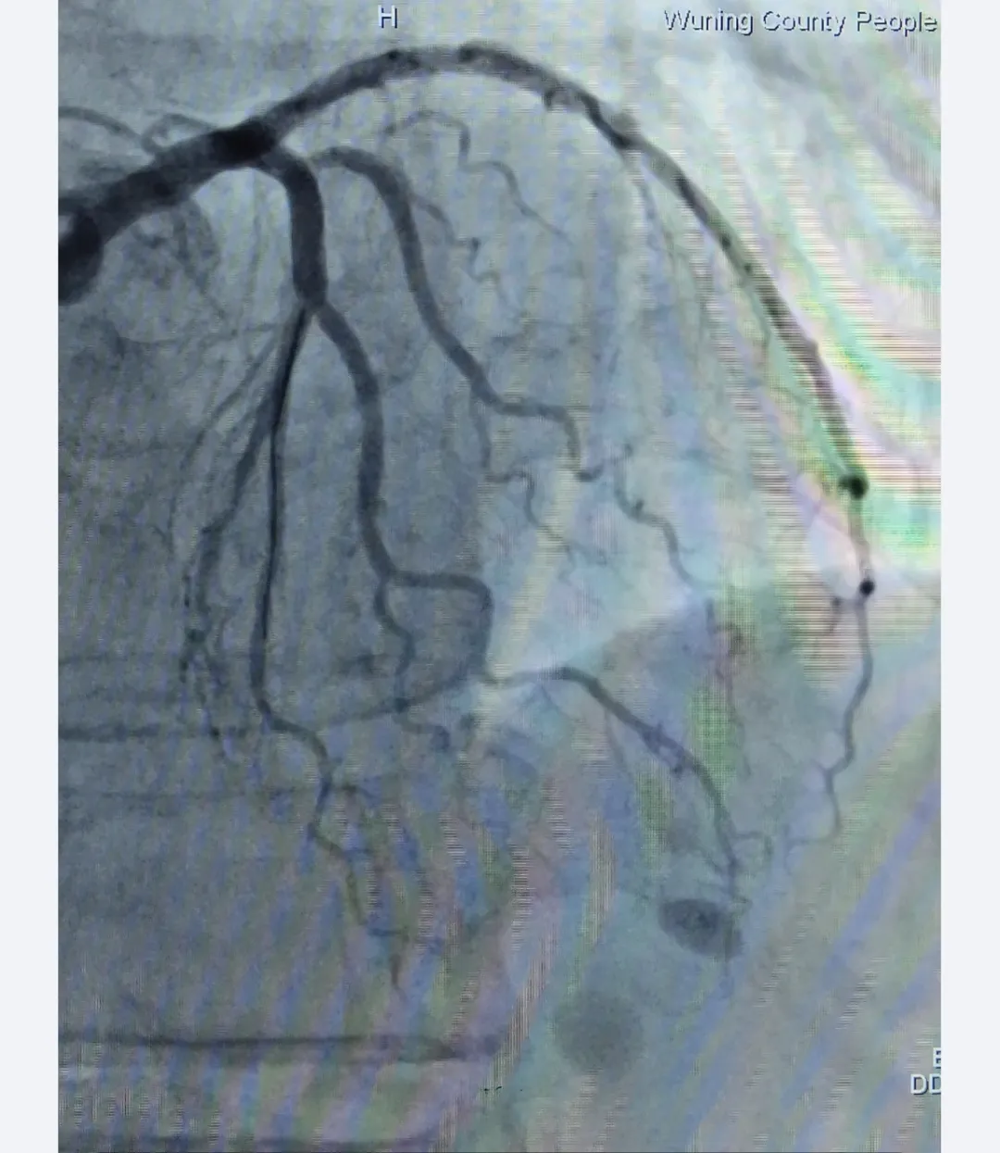

支架植入后